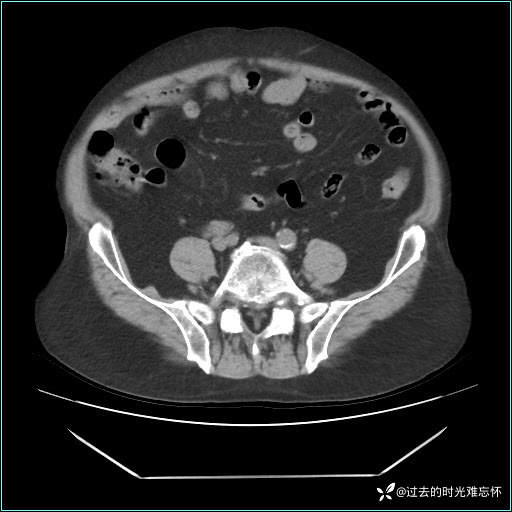

患者男,71 岁,因「反复腹痛腹胀 1 月」入院。

现病史:患者 1 月前无明显诱因下出现腹痛腹胀症状,腹痛呈隐痛,当时未予以重视,后症状有所加重,常在进食辛辣刺激油腻等食物后出现腹痛,口服药物治疗症状能得到控制,病情控制一般。现为求诊治来我院,拟“腹痛”入院。病程中患者神志清楚,精神一般,无咳嗽咳痰,无恶心呕吐,近期体重无明显变化。